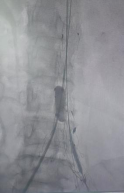

栓塞肠系膜下动脉

释放左髂内动脉分支

之家释放后扩张